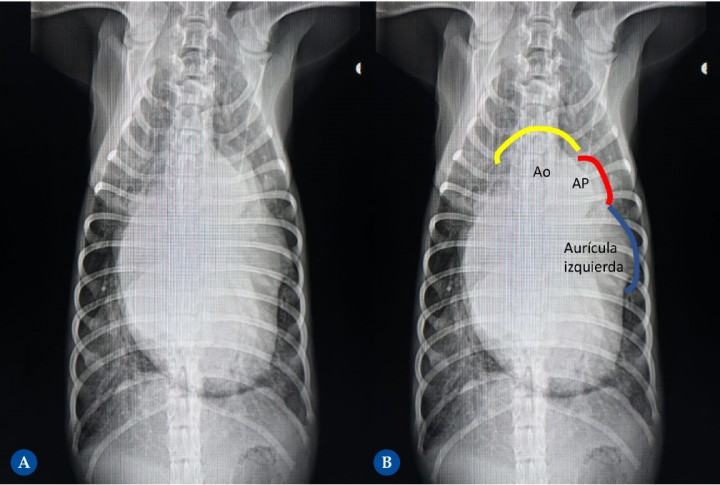

<p>Cachorro de Bretón de 4 meses remitido en fallo cardíaco congestivo debido a la presencia de un conducto arterioso persistente. (<strong>A</strong>) Proyección ventrodorsal. (<strong>B</strong>) Diagrama donde se marca sobre la imagen A las proyecciones anatómicas del "triple knuckle" según la analogía del reloj. Se observa cardiomegalia severa con “triple knuckle” debido a la dilatación marcada del cayado aórtico (de 11 a 1 h), la arteria pulmonar (de 1 a 2) y la orejuela del atrio izquierdo (de 2 a 3). Los bronquios principales caudales están separados entre ellos debido al gran tamaño del cuerpo del atrio izquierdo, dando lo que coloquialmente se llama “las piernas del vaquero”. El ápex izquierdo se ve redondeado y apoyado ampliamente sobre el diafragma, consistente con la presencia de dilatación ventricular izquierda severa. Congestión venosa y patrón pulmonar intersticial generalizado son signos de insuficiencia cardíaca congestiva izquierda. Línea de color amarillo: de 11 h a 1 h. Línea de color rojo: de 1 h a 2 h. Línea de color azul: de 2 h a 3 h. Ao: aorta. AP: arteria pulmonar.</p>

Cachorro de Bretón de 4 meses remitido en fallo cardíaco congestivo debido a la presencia de un conducto arterioso persistente. (A) Proyección ventrodorsal. (B) Diagrama donde se marca sobre la imagen A las proyecciones anatómicas del "triple knuckle" según la analogía del reloj. Se observa cardiomegalia severa con “triple knuckle” debido a la dilatación marcada del cayado aórtico (de 11 a 1 h), la arteria pulmonar (de 1 a 2) y la orejuela del atrio izquierdo (de 2 a 3). Los bronquios principales caudales están separados entre ellos debido al gran tamaño del cuerpo del atrio izquierdo, dando lo que coloquialmente se llama “las piernas del vaquero”. El ápex izquierdo se ve redondeado y apoyado ampliamente sobre el diafragma, consistente con la presencia de dilatación ventricular izquierda severa. Congestión venosa y patrón pulmonar intersticial generalizado son signos de insuficiencia cardíaca congestiva izquierda. Línea de color amarillo: de 11 h a 1 h. Línea de color rojo: de 1 h a 2 h. Línea de color azul: de 2 h a 3 h. Ao: aorta. AP: arteria pulmonar.